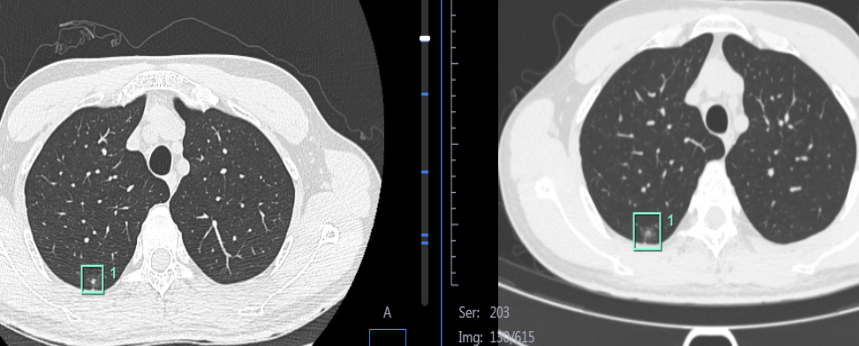

谁懂啊!坏情绪真的让人长结节 当代年轻人除了一身反骨,体检报告上建议复查随访的小部位是越来越多了。 打工人共勉:这身体不想要了! 小方父亲因肺癌去世 他在一次常规的体检CT中 被确诊为肺结节 四处求医 各方说法均不得安心 最后 还得是这双火眼金睛 拿下野蛮生长的“它” 两年前,三十岁的小方(化名)在深圳某三甲医院进行体检做胸部CT检查时,结果显示“右上肺磨玻璃结节,直径约1.2cm”,确诊为肺结节。 这一结果给小方吓一跳——父亲多年前因肺癌去世,给小方敲响警钟。 根据Fleischner Society[1]发布的成人偶发性肺结节的处理指南建议: 对于年龄大于35岁的低风险成人,直径≤6mm的实性和亚实性结节,通常不需要进一步随访。 对于直径大于6mm的结节或多发的磨玻璃结节,建议携带检查资料(必须带CT胶片)到专科门诊进行咨询。 医生通常只对一些随访过程中增大的、怀疑发生恶变的病灶进行手术切除。 这两年来,尽管小方没有咳嗽、咳痰、胸痛等不适症状,但依旧采取保守观察,定期随访。 一年多以来,四次CT检查,肺结节到底有没有长大? 这困惑从发现那天起就一直萦绕在小方的内心深处。 回想父亲发现肺癌后手术效果不理想,不久后就去世,小方对手术治疗还是相当抵触。 四处求医,跑了省内多家名专医,医生们对肺结节的判断都有自己的标准,都不能给出令小方安心的治疗方案。 求医心切的他通过网络冲浪搜索“肺结节”,弹出的第一个↓ 深圳市第三人民医院胸外科主任乔坤 于是小方抱着试一试的心态来到了深圳市第三人民医院胸外科。 看着眼前的年轻小伙满脸焦虑,胸外科主任乔坤告诉小方: 肺结节≠肺癌,不是所有的肺结节都会发展成为癌。 ▼ 2017 版 Fleischner 指南 针对成年人偶然检出肺结节的管理建议 经过我院肺结节多学科诊疗团队讨论,小方右肺上叶后段胸膜下混合磨玻璃结节,大小约1.2cm,可见小支气管及血管影穿行,边界清晰,邻近胸膜牵拉,考虑高危结节。 小方还把外院原始CT数据拷贝了过来,经过对比测量,初步判断22个月来结节直径未见明显变化。 但由于肺结节为球状体,单纯计算长径无法精确评估,为避免人工误差,乔坤团队使用最新的AI软件,对比小方第一次和最近这次的胸部CT↓ 可见结节体积分别为204.4、312.3mm3 结果显示:结节体积相比较最初是增大的。并且小方存在肺癌家族史,建议手术治疗。 由于结节位于外周,以磨玻璃成份为主,CTR<0.5,建议手术方式行单孔胸腔镜右上肺部分切除术,既切除结节,又最大程度的保留肺功能。 经过与小方及家属的耐心沟通,打消了顾虑,同意手术。 今年6月,在我院行“胸腔镜右上肺部分切除术+纵隔淋巴结采样术+肋间神经阻滞术”。 术后当天2小时后可下地活动,术后第1天,可走5000-8000步,复查胸片等报告显示达到出院标准。 术后,乔坤主任回顾—— 小方右肺上叶后段胸膜下混合磨玻璃结节,结节在随访中看似稳定,其实在暗地里偷偷生长,22个月里体积长大了1/2,术后病理提示“浸润性腺癌”,并且存在 “气道播散”高复发因素,继续随访的话,后果将不堪设想。 所以,虽然磨玻璃结节大多数是惰性的,但不可轻视,在你见不到的背后,可能野蛮生长。 03遇到肺结节该怎么办 查出肺结节的人越来越多,是因为做检查的人变多了,检查技术也进步了。 有些地方用了更好的技术,肺结节的发现率更高。 或许每个人身边都有几个朋友体检查出了肺结节。 但这并不意味着肺部结节的发病率在明显升高,不必过度恐慌。 01 如果你不属于高危人群,恶性风险又低了一些。 据 2021 版的《居民常见恶性肿瘤筛查和预防推荐》建议,高危人群是指年龄大于 40 岁的,且具有以下任一危险因素的人: ? 吸烟每天一包持续20年或每天2包持续10年,其中包括戒烟时间不足15年者; ? 长期被动吸烟者; ? 有职业暴露史(石棉、铍、铀、氢等接触者)者; ? 家族中有恶性肿瘤或者肺癌患者; ? 有慢性阻塞性肺疾病或弥漫性肺纤维化病史者。 在肺结节的检出率上,普通人群和高危人群其实差不多[2],只是高危人群检出肺结节的恶性概率更高一些。父亲因肺癌去世小伙得肺结节四处求医